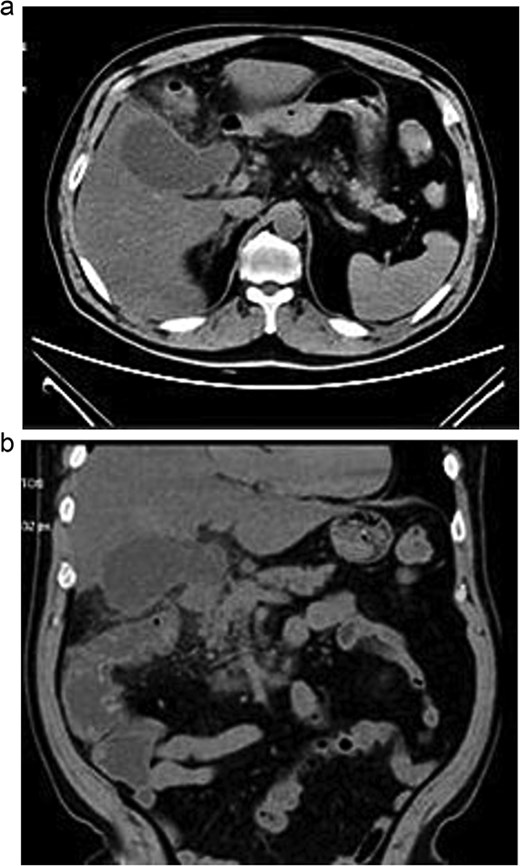

Lab tests showed leukocytosis (15.2 × 103/μl), thrombocytopenia (95.8 × 103/μl), elevated CRP (25.22 mg/dl), procalcitonin (4.49 ng/ml), and total bilirubin (3.5 mg/dl). Liver function was otherwise normal. Ultrasound revealed lithiasic cholecystitis with hydrocholecystosis. Computed tomography (CT) failed to detect duplication (Fig. 1a and b). MRCP confirmed H-type duplicated gallbladder with two independent cystic ducts and mild extrinsic compression of the extrahepatic bile duct (Mirizzi-like pattern) (Figs 2 and 3). MRI sequences (T1 LAVA-Flex and T2 PROPELLER with fat suppression) also demonstrated the duplicated gallbladder and supported the MRCP findings (Fig. 4). No choledocholithiasis was seen.

MRCP showing duplicated gallbladder (H-type), with two independent cystic ducts draining into the common bile duct.